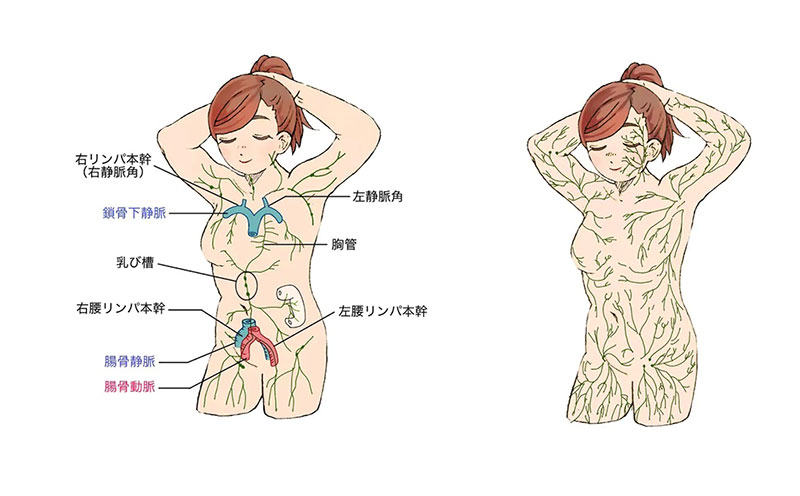

全身に張り巡らされたリンパ管は細胞・組織の間の体液を取り込んで、リンパ液としてそれを運んでいます。リンパ管は動脈や静脈とは異なる流れ方をしており、とても細かく張り巡らされたリンパ毛細管が組織間液を吸収し、太いリンパ管に合流し、最後は首の部分で静脈に合流します。

ほとんどの場合、首の左側の静脈には下半身と左上半身からのリンパ管がつながり、右の静脈には右上半身のリンパ管がつながっています。

リンパ管について

リンパ管は、主に皮下脂肪の中にある細い表在リンパ管と、頸部・腋窩部(わきの下)・鼠径部(足の付け根)にあるリンパ節、腹腔や胸腔から首まで達する深部リンパ管があります。

表在リンパ管は全身の皮下組織にきめ細かく張り巡らされていますが、その流れには体液区分線という境界線があり、それに従ってどのリンパ節に流れ込むかがが決まっています。体液区分線は、身体の中央、鎖骨へその上下などにあります。

重力に逆らってリンパ液を首まで運ぶため、リンパ管には自動運動能や逆流防止弁があり、筋肉ポンプの働きも利用しています。